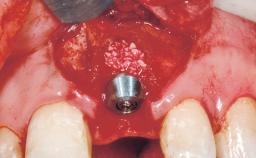

Immediate Flapless Placement of an Implant in a Maxillary Left Central Incisor Site

A 29-year-old female patient presented for treatment to replace the upper left central incisor tooth with an implant- supported restoration. The tooth had been intermittently symptomatic for the previous 12 months. The tooth had originally suffered trauma about 15 years previously. Several endodontic treatments had been performed, including an apicectomy procedure to retain the tooth. The patient was healthy and a non-smoker. She had reasonable expectations in regard to esthetic outcomes and the risk of marginal tissue recession following treatment. At medium smile, the gingival margins of the upper teeth were visible, with a display of 3 to 4 mm of the gingival margins. Gingival recession of tooth 21 and a discrepancy in the gingival levels between teeth 11 and 21 was observable during normal speech and smile.

Placement Protocol Immediate implant placement

Socket Morphology Single-root socket

Socket Integrity Damage to one or more bone walls

Bone Volume Damage to one or more socket walls